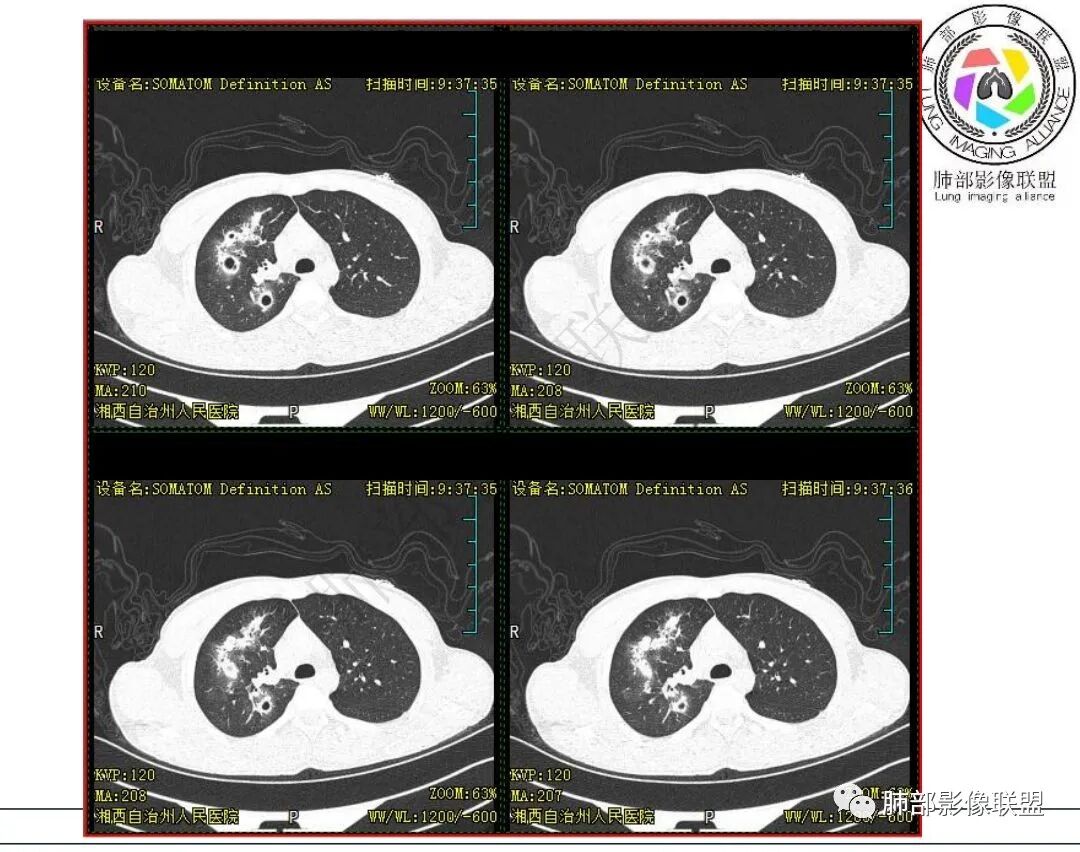

影像:右肺上叶多发实变影结节影,边界模糊,边缘收缩,伴多发空洞,洞壁光滑,部分支气管壁增厚。

3.首次CT提示:右肺上叶多发结节影及实变影,簇状分布,周围散在磨玻璃影,结节内多类圆形空洞,内壁光整,有一定张力,偶见液平。部分支气管壁增厚。

考虑良性感染性病变可能。